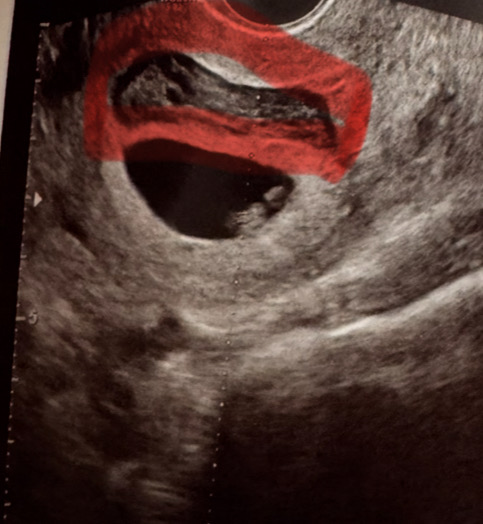

시험관 동결배아이식(3개) 한주씩 확인할때마다 늘어나서 네둥이가 됐습니다. 지금 6주3일차입니다. 어제 생리2일차 처럼 저녁부터 새벽내내 흐르고 해서 오늘 병원다녀왔더니 다행히 세명은 심박수 열심히 잘 뛰더라구요(125bpm) 1명은 제일 늦게 나타난 아인데 지금은 아기집만 있습니다 이렇게 피고임이랑 출혈 있어도 잘 유지 될까요?ㅠㅠ

제가 3주 걸쳐서 네둥이 확인했었답니다🥹 처음에는 아기집2개 다음에 난황2 아기집1 다음에 심소2, 난황1, 아기집1 최근 심소3, 아기집1 이렇게 확인했었답니다🥹